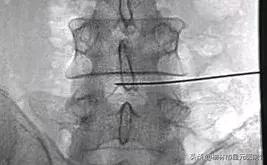

术前定位

手术中